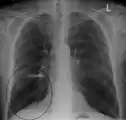

فقاعة بالرئة عند مريض لديه مريض الـ COPD